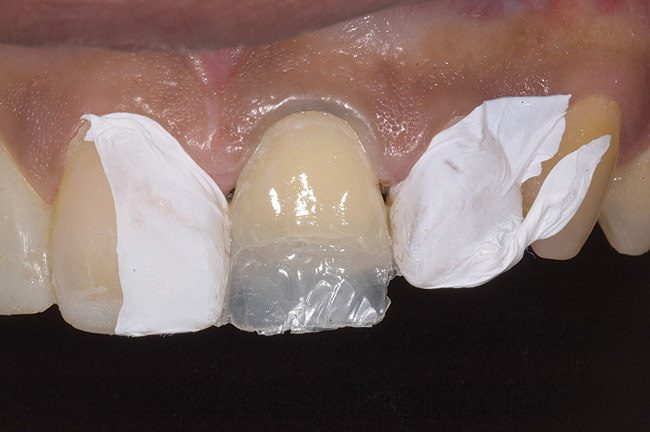

Figure 10  Tooth No. 9 with no preparation on the palatal surface to restore lost form with bonding resin.

Figure 10

During the next appointment, a palatal index of the approved provisional was fabricated with putty silicone. This enabled the clinician to precisely build the lingual surfaces and incisal edges of teeth Nos. 6 through 11. The provisional mock-up resin on No. 9 was removed, and the underlying labial tooth was roughened with an abrasive diamond bur. No tooth structure was removed from the palatal surface, and unsupported enamel was rounded off from the labial. An ultrathin dry cord was placed in the gingival sulcus on No. 9 (Figure 9 and Figure 10). Teflon tape was used to isolate No. 9 from adjacent teeth. Then 37% phosphoric acid was used to totally etch the labial surface for 10 seconds and the palatal surfaces on No. 9 for 5 seconds. Single bond was applied and spread uniformly across the tooth and light-cured for 20 seconds.